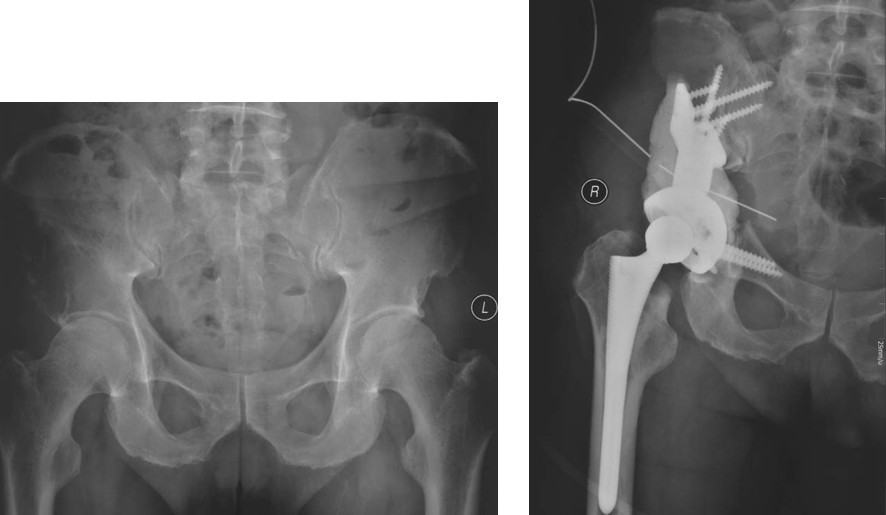

图2,女,31岁,乳腺癌髋臼转移, Harrington I型

图3,女,55岁,肺癌髋臼转移, Harrington II型